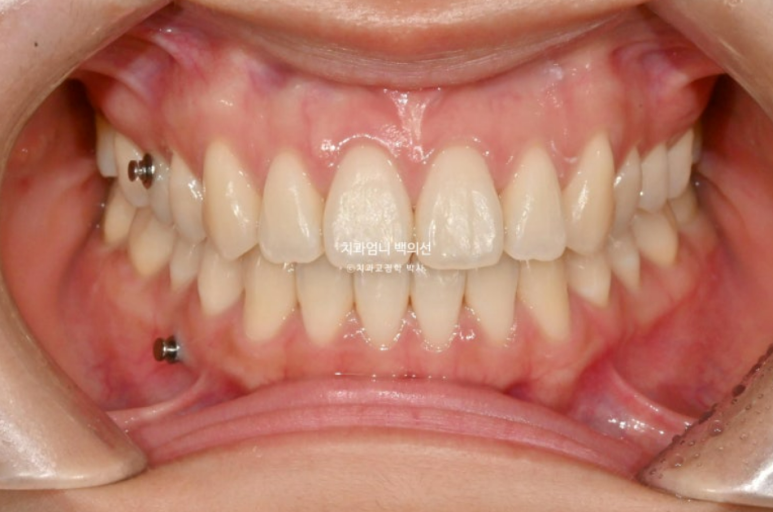

25년 4월 치료를 마무리 했습니다. 중심선은 이제 정확히 맞습니다.

철사유지장치 부착 후 환자분은 가철식 유지장치로 비베라를 선택했는데 비베라 제작을 기다리는 2주동안 사진상 메탈고리와 하악 미니스크류 사이에 고무줄을 걸면서 초진시 떠있던 해당치아의 교합을 유지합니다.

처음에 들려있던 치아라 철사유지장치 부착 후 아무 장치도 안 끼기 시작하면 재발에 의해 미세하게 다시 들리기 때문입니다.

어금니 교합은 좋습니다.

이제 전 후 비교 보겠습니다.

배열은 좋으며 철사유지장치까지 붙은 모습입니다.

이제 어금니 함입에 의한 하악골 자가회전 효과를 보겠습니다.

실눈 뜨고 보면 처음에 비해 하관이 약간 짧아지며 턱끝이 약간 나오고 도툼해졌습니다.